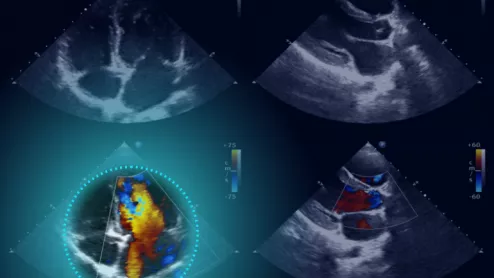

Echo:Prio represents the latest addition to Dyad Medical's cloud-based Libby platform. Image courtesy of Dyad Medical.

AI can help care teams identify heart patients who would benefit from TAVR or another life-changing valve intervention.